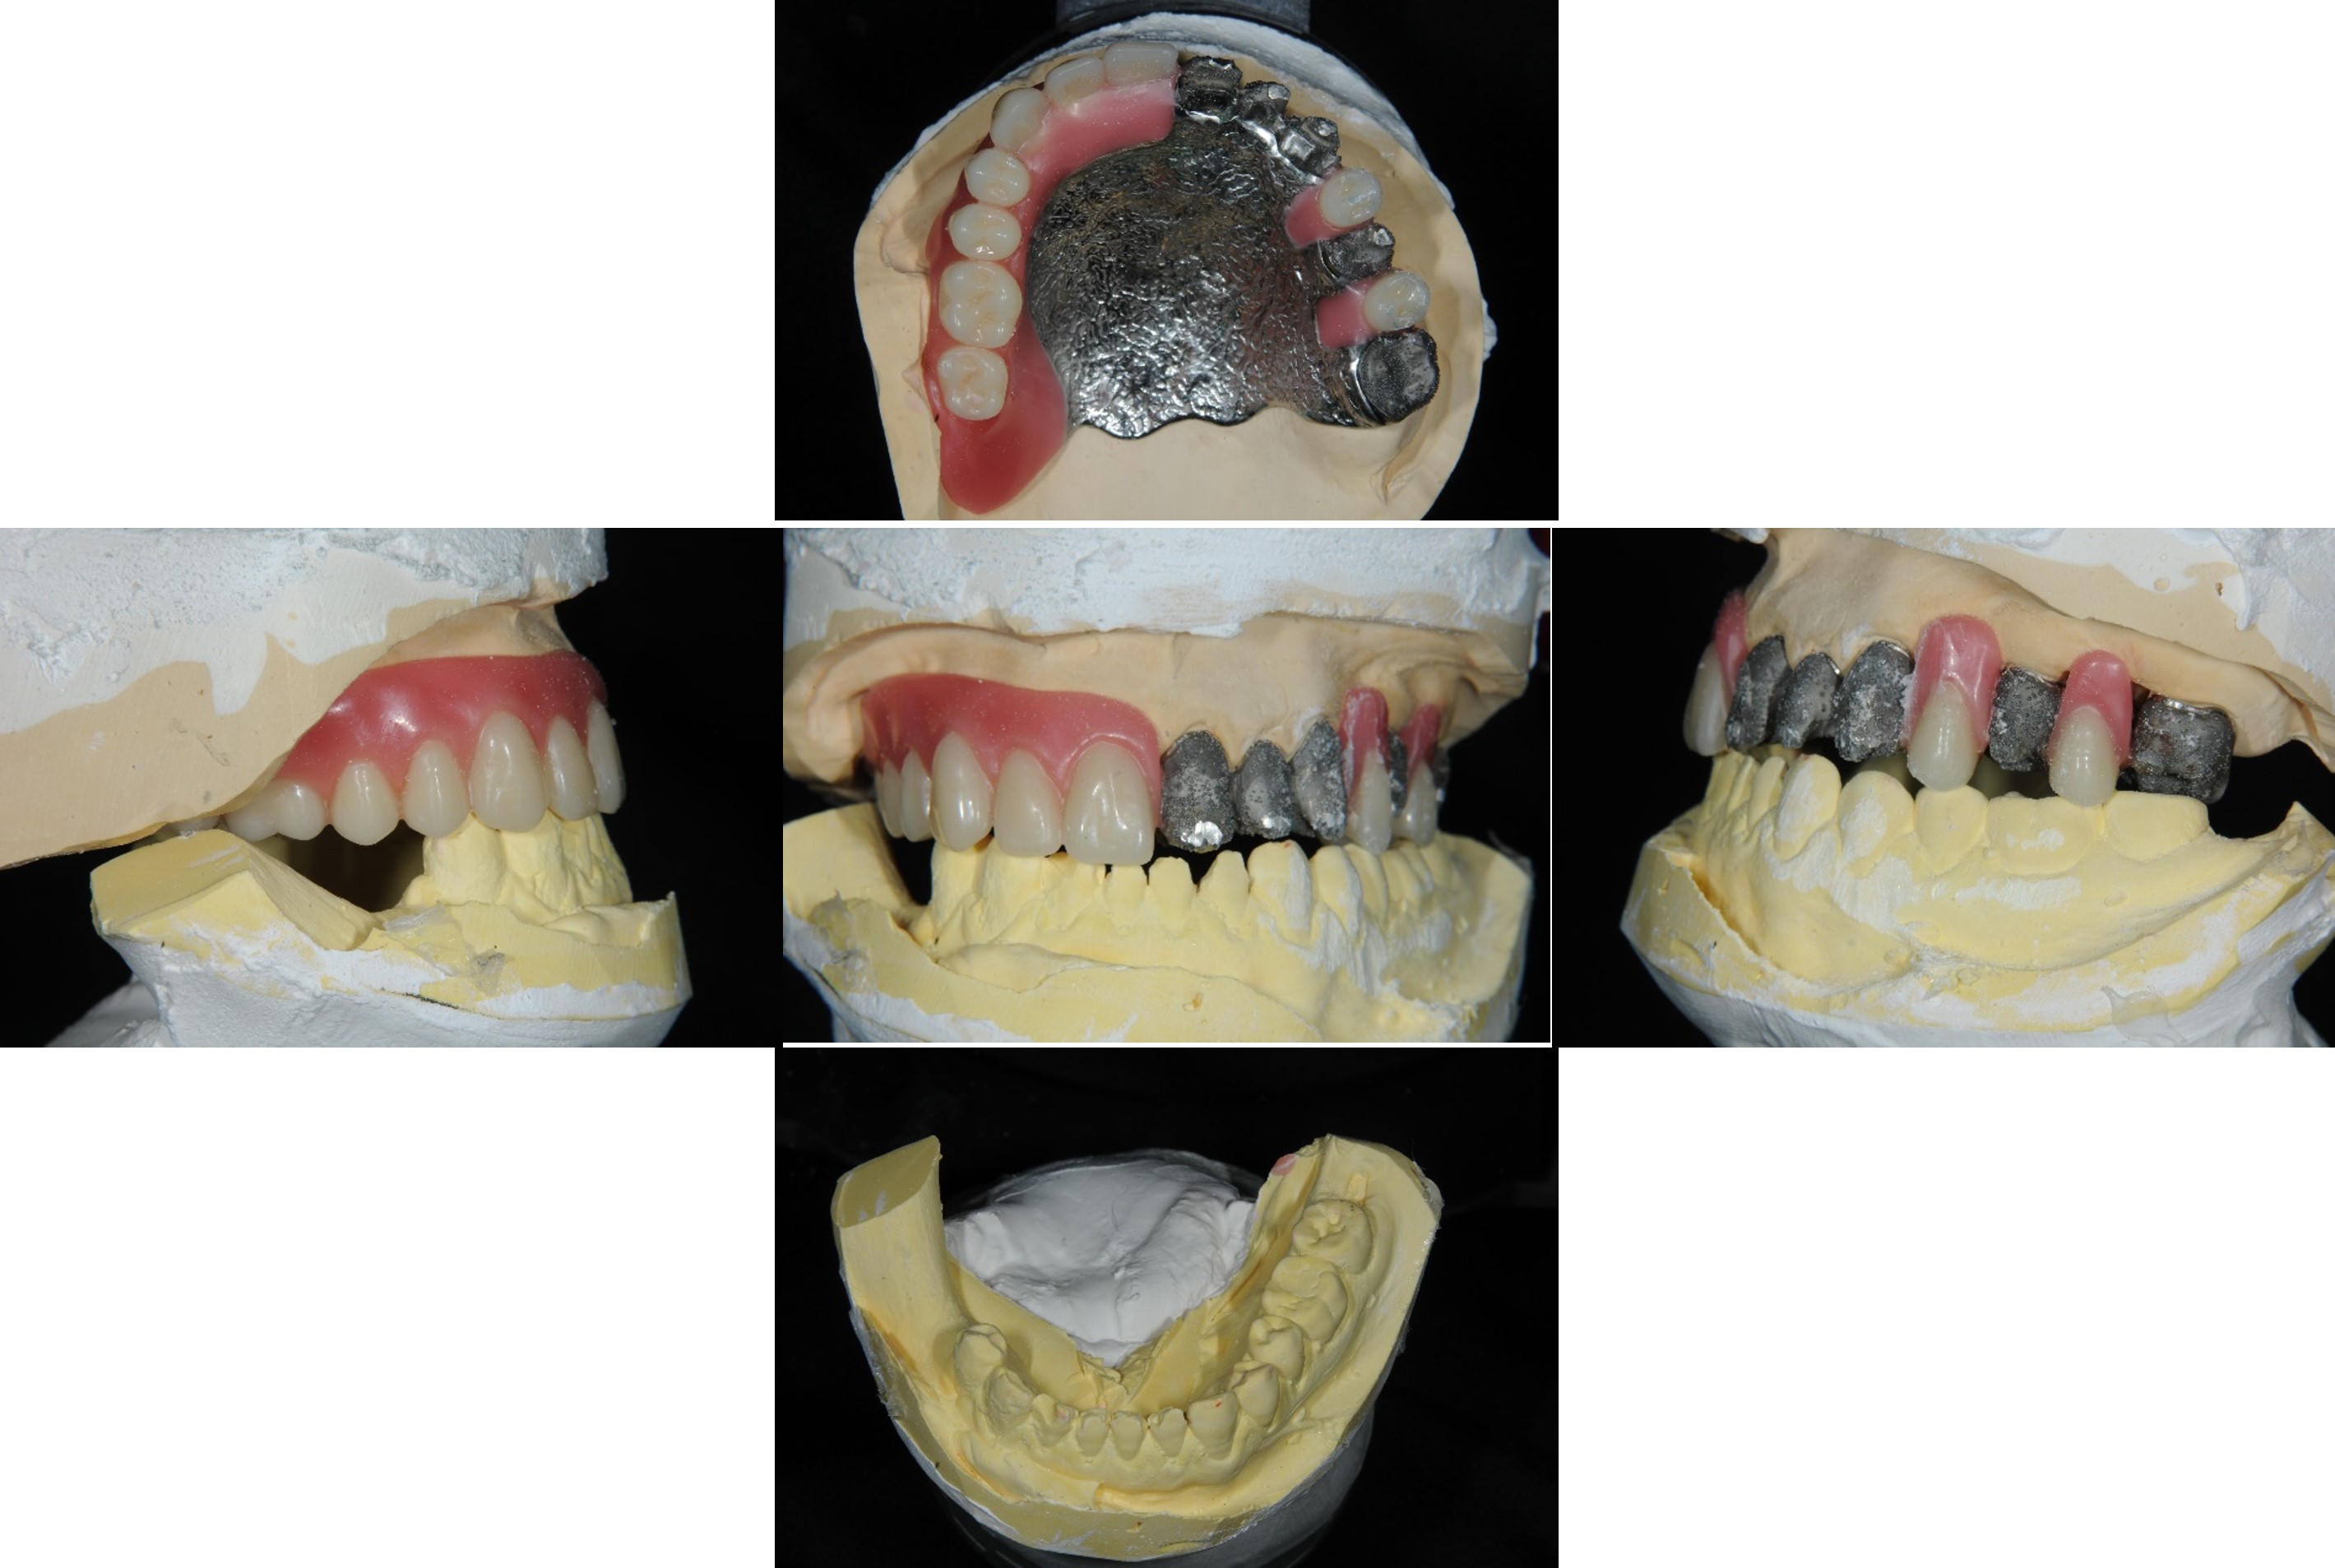

內外冠及活動假牙

組合後外冠及活假牙套件

外冠及活動假牙套件

活動假牙套件

內外冠支撐活動假牙